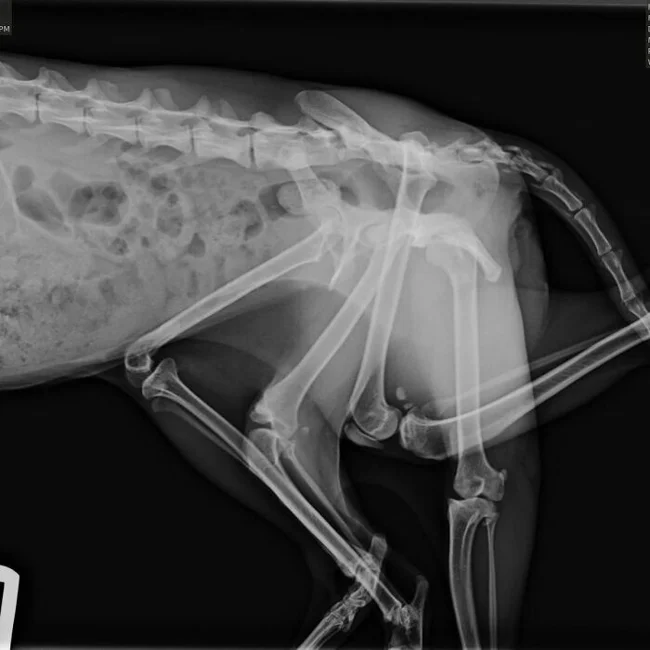

В клинике Windermere ветеринары сделали рентгеновские снимки Битси. Они решили, что операция поможет ей чувствовать себя лучше

Кошка перенесла сложную операцию по удалению лишних конечностей и таза